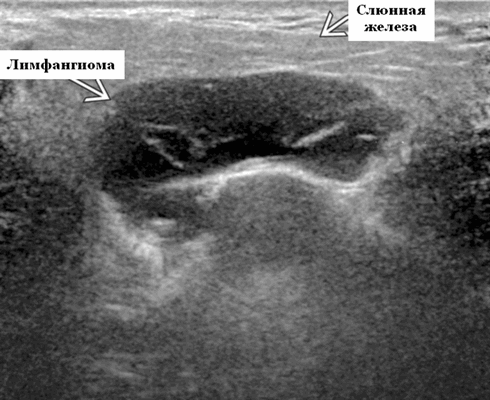

- Расположение. 75% возникают в области головы и шеи (наиболее часто). На подъязычной области шеи ЛМ чаще всего встречаются в заднем треугольнике, тогда как жевательные и поднижнечелюстные пространства - самые частые места надподъязычной зоны шеи. Интрапаротидное расположение встречается нечасто, при этом поражение может быть транспространственным, затрагивая несколько смежных пространств. 20% поражают опухолей подмышечную впадину. Реже поражается средостение, пах и забрюшинное пространство.

- Морфология. Однокамерное или, чаще, многокамерное поражение. Может содержать округлые или вкрапленные кистозные пространства. Имеет тенденцию проникать между нормальными структурами без какого-либо масс эффекта

Результаты ультразвукового исследования. Серошкальное УЗИ. Более крупные околоушные лимфангиомы могут быть обнаружены при пренатальном УЗИ. Чаще мультилокулярный, чем монокулярный. Кистозные пространства могут быть округлыми или вкраплениями. Поверхностные поражения сжимаются ультразвуковым датчиком. Внешний вид зависит от того, было ли ранее кровотечение / инфекция. Негеморрагический / неинфицированный лимфаангимоы выглядят на УЗИ как однокамерные или многокамерные (чаще) анэхогенные сжимаемые кисты с тонкими стенками и промежуточными септами. Несмотря на большие размеры, существенного масс эффекта нет. Тонкие незаметные стенки с задним акустическим усилением. Цветной допплер: в области поражения нет кровеносных сосудов. Геморрагический / инфицированный тип лимфатической мальформации. Однокамерные или многокамерные гетерогенные кисты с неровными стенками, внутренним дебрисом. Несжимаемые датчиком и гипоэхогенные полости с толстыми стенками и перегородками. Уровни жидкости-жидкости из-за осаждения и разделения жидкостей предполагают предшествующее кровотечение. Цветной допплер: при заражении; васкуляризация может быть видна в стенках, перегородках и прилегающих мягких тканях